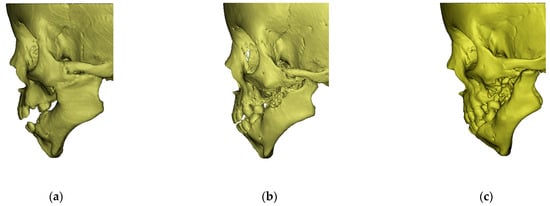

3.1. Prior to the Commencement of Treatment (Age—16 Months)

- left side larger than the right side; both the surface area and the volume were asymmetrical toa moderate degree (Table 4 and Table 5). Figure 4 shows the differences revealing asymmetrical structure of the mandibular bone in relation to the median sagittal plane. The greatest deviations from the symmetrical build exceeded 5 mm;

- asymmetry toa moderate degree, which revealed itself in the difference in the total length of the mandible (Table 5). Length gn–kdl on the left side (affected by ankylosis) was shorter than that on the right side (AI = 5.05%);

- moderately asymmetrical angles of the mandible; gonial angle (alpha) on the right side was larger by eightdegrees than the left angle (Table 5).